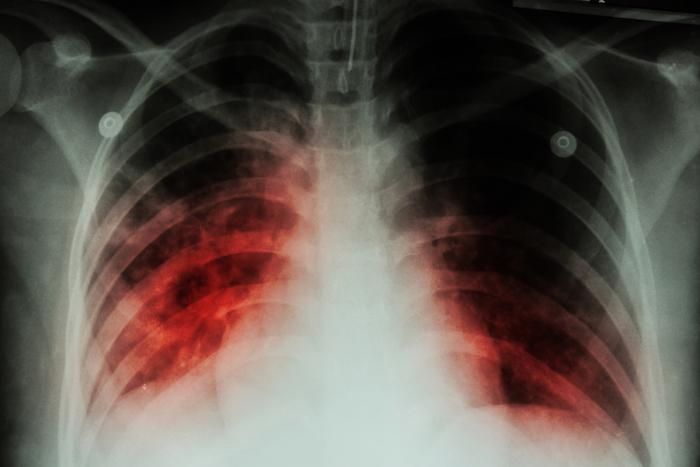

La tuberculose est une maladie contagieuse qui se transmet par voie aérienne, parfois une simple toux ou un éternuement. Elle se manifeste par des symptômes respiratoires, ainsi que de la fièvre, des sueurs, un amaigrissement. Elle se soigne avec des antibiotiques.